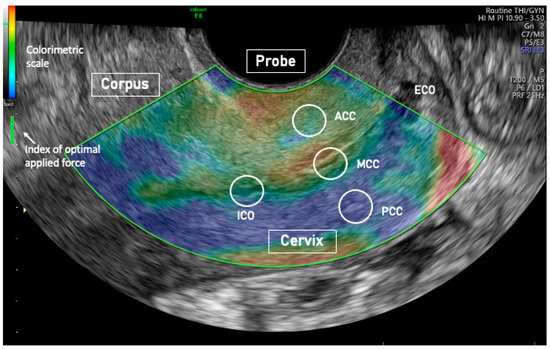

| ACC elasticity | 0.94 ± 0.36 |

| PCC elasticity | 0.74 ± 0.29 |

| MCC elasticity | 1.39 ± 0.51 |

| ICO elasticity | 0.63 ± 0.28 |